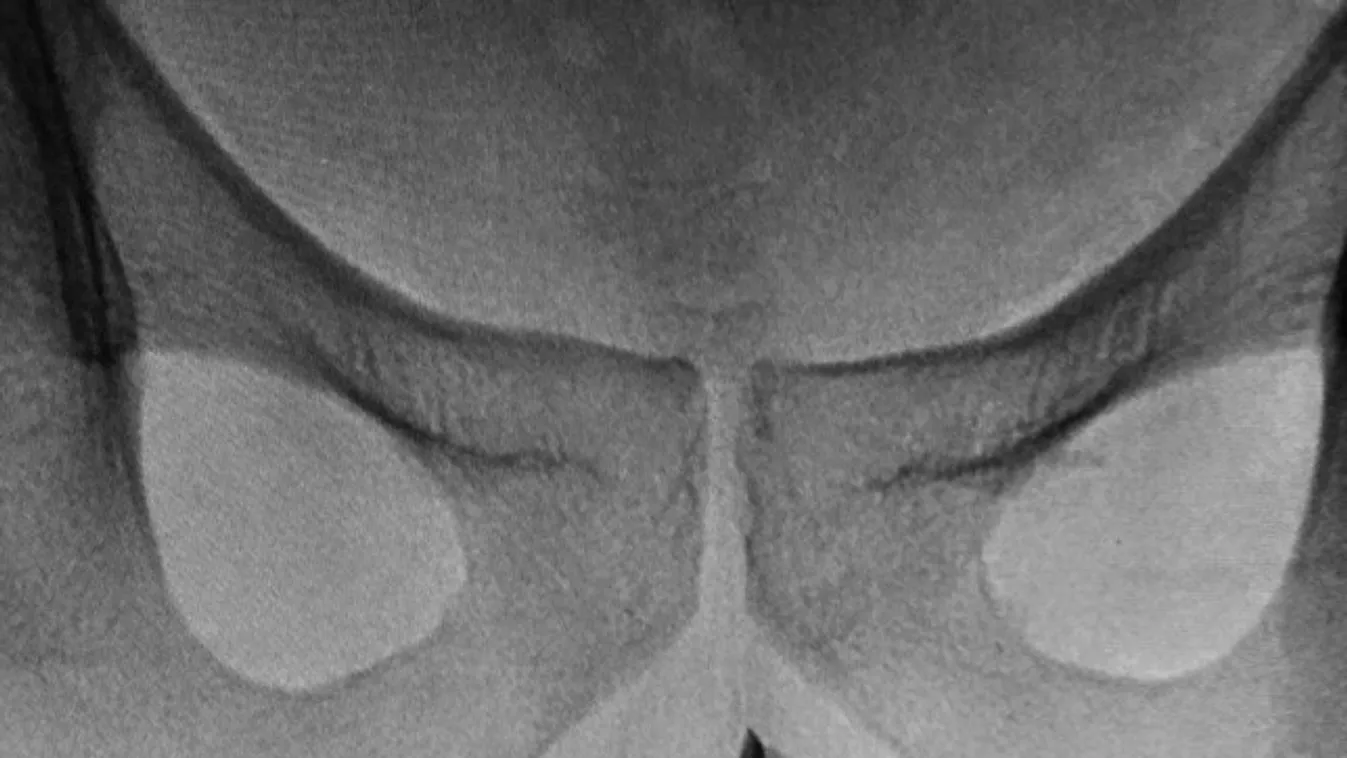

A 8 centiméter hosszú csipesz eltávolításának egy kisebb orvosgárda látott neki. A műtét nem volt könnyű, mivel a csipesz nyitott vége könnyen felsérthette volna belülről a beteg péniszét kihúzás közben. A körülményekre való tekintettel végül altatás mellett döntöttek az orvosok, nehogy a páciens hirtelen reakciói még nagyobb bajt okozzanak műtét közben. A beavatkozás annyira sikeres volt, hogy a beteget még aznap haza is engedték a kórházból.

Az orvostudományi feljegyzésekben alapján ez volt a második eset, amikor egy csipeszt kellett eltávolítani valakinek a húgycsövéből.